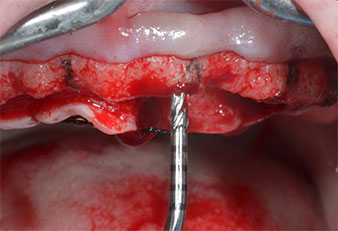

A flame-shaped, diamond-coated piezoelectric instrument (Piezomed I1) was used to mark the implant positions and to perform pilot preparation (Fig. 3). Care was taken to use an up and down movement, with reduced power, full irrigation and low pressure (below 300 g). Next a pilot instrument (Piezomed I2A/I2P) was applied for the initial 2 mm diameter enlargement of the implant sites (Fig. 4), followed by a 3 mm insert (Fig. 5).

Piezomed I2A/I2P instruments

Fig. 4: The next step is pilot enlargement with the Piezomed I2A/I2P instruments, which are applied in a rotary horizontal movement.